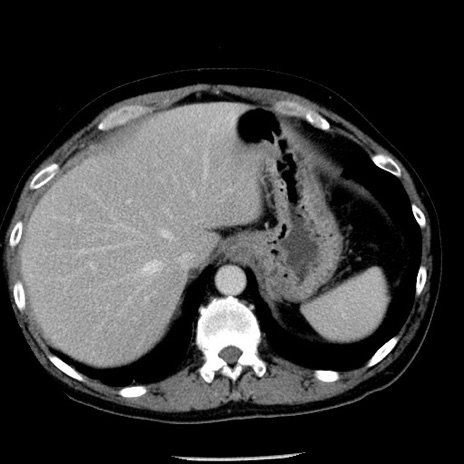

症例29(横断像)

【症例】40歳代男性

【現病歴】2日前から胃痛あり。徐々に周期的な激痛に変化した。本日になっても激痛があるため受診。

【身体所見】意識清明、BT 38-39℃台あり、腹部:膨満、やや硬、右下腹部に圧痛あり。

【データ】WBC 8500、CRP 23.26